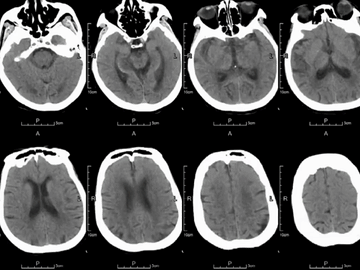

急诊CT:左侧MCA主干局部管腔重度狭窄,分水岭区血流减慢,CT平扫ASPECT-10。

静脉溶栓后症状加重,NIHSS_10